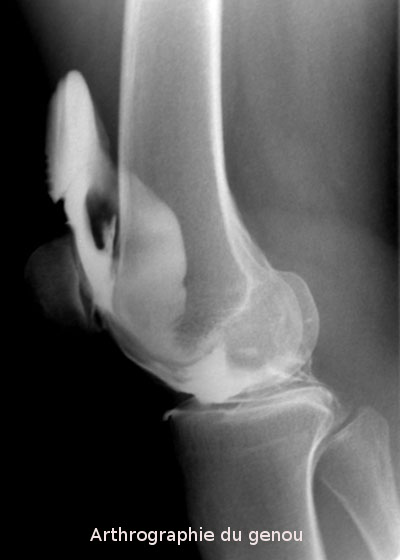

L'arthrographie est un examen radiologique consistant à introduire un produit de contraste en intra-articulaire (apparaissant en blanc sur les clichés) afin de démontrer l'intégrité ou la présence de lésions de structures intra-articulaires comme les cartilages, les ligaments, etc.

L'arthrographie est donc une technique qui utilise les rayons X et des agents de contraste qui sont en principe à base d'iode. Les articulations les plus fréquemment examinés sont l'épaule,le genou, le poignet, la hanche et la cheville.

genou (déchirures méniscales, lésions ligamentaires, évaluation du cartilage)